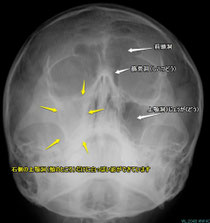

1.急性副鼻腔炎

風邪を引いた時に、色のついた鼻水が出て来たり、頬や眉間が痛くなったりします。

2.慢性副鼻腔炎

一般的によく言われる「蓄膿症」もこれに含まれます。

a)慢性化膿性副鼻腔炎

感染後の粘膜の腫れによって、副鼻腔への交通路が狭くなることで起こります。色のついた鼻水がでたり、のどの方に流れて来たりします。ただ感染が落ちついている時は白っぽい粘稠の液が溜まっていることもあります。